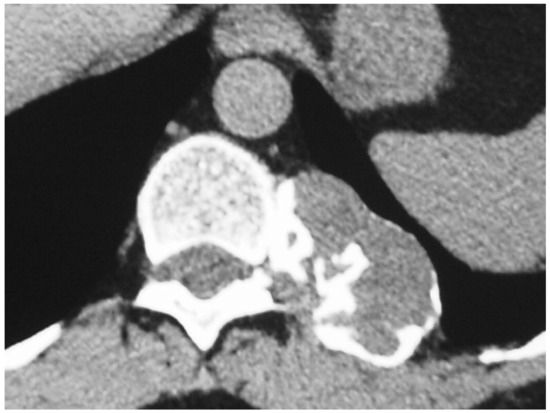

Grade 1 and 2 Chondrosarcomas of the Chest Wall: CT Imaging Features and Review of the Literature

3. Results